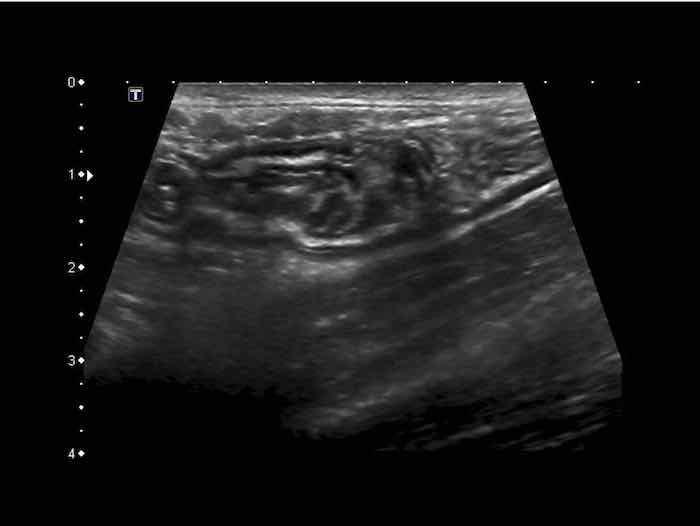

Đây là hình ảnh siêu âm của một trẻ 2 tuổi bị lồng ruột hồi manh tràng từng đợt, được khám trong khoảng thời gian giữa các cơn.

Hồi tràng với nhiều mảng Peyer sa vào manh tràng.

Hình ảnh siêu âm kinh điển của lồng ruột hồi-manh tràng ở hai trẻ khác nhau.

Trong cả hai trường hợp, đoạn hồi tràng bị lồng được định vị không đối xứng bên trong ống lồng ngoài, do mạc treo ruột tăng âm có chứa mỡ, bám vào hồi tràng và đi theo hồi tràng khi bị kéo vào trong.

Trong mạc treo, siêu âm cho thấy một hạch bạch huyết mạc treo (hbh) phóng đại ở cả hai.

Các hạch này phì đại như một phần của tình trạng tăng sản hạch bạch huyết toàn thân và khônghu trú trong lòng hồi tràng.

Do đó đây không phải là điểm dẫn đầu nguyên phát. Ở bệnh nhân bên phải, ruột thừa (mũi tên) cũng bị kéo vào trong.

Lưu ý cấu trúc đa lớp của thành bụng phía trước của phức hợp lồng ruột, đại diện cho ba lớp thành ruột bị gấp lại.